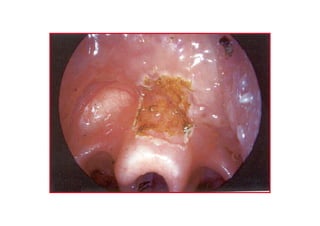

AnteriorAnterior komisskomissüürr caca

T1T1 glottikglottik larenkslarenks caca

T3T3 glottikglottik larenkslarenks caca